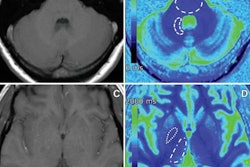

Images show differences in image quality based on the amount of gadolinium-based contrast administered. Courtesy of Gong et al and RSNA."With a large dataset, we demonstrated the deep-learning solution can generalize well, achieving robust and significant quality improvement over the low-dose contrast-enhanced MRI, using 10% or even less gadolinium dosage," the researchers concluded. "Low-dose gadolinium images yield significant untapped clinically useful information that is accessible now by using deep learning and AI."

Neuroradiologists then evaluated the images based on contrast enhancement and overall diagnostic quality. They found that image quality did not differ significantly between the synthetic full-dose images produced by the deep-learning algorithm and the actual full-dose images. What's more, the results showed the potential for creating the equivalent of full-dose images without using a contrast agent, according to the researchers.